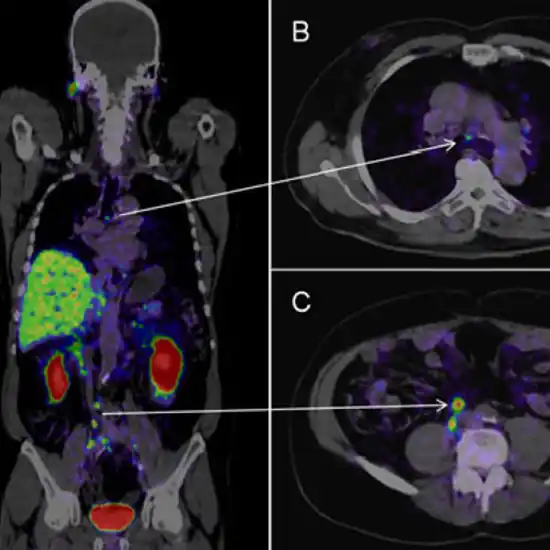

PSMA PET scan for prostate is the diagnostic procedure used to detect prostate cancer anywhere in the body. PSMA is the short form of prostate cancer membrane antigen, this is the type of membrane antigen that is present on the surface of cells having prostate cancer. PSMA PET scan CT is a sensitive scan available at only certified diagnostic centres to detect prostate tumours. This ground-breaking test is capable of seeing even the smallest tumours which can be missed in other tests of diagnosis.

Prostate-Specific Membrane Antigen (PSMA) PET scan is a medical imaging technique that aids in evaluating whether prostate cancer has spread outside the prostate gland or not. This imaging technique combines a type of sugar as a radioactive tracer with the specialized camera to obtain detailed images of the prostate gland. The scan specifically targets the prostate-specific membrane antigen, a protein found in high concentrations in prostate cancer cells. The radioactive tracer bins to the PSMA and lights up on the scan.

The PSMA is used as the phenotypic biomarker with the positron emission tomography (PET) imaging options. The PSMA could be over- expressed in cases of metastatic prostate cancer, which is relative to the normal tissue thus, is present in >80% of the men suffering from prostate cancer.